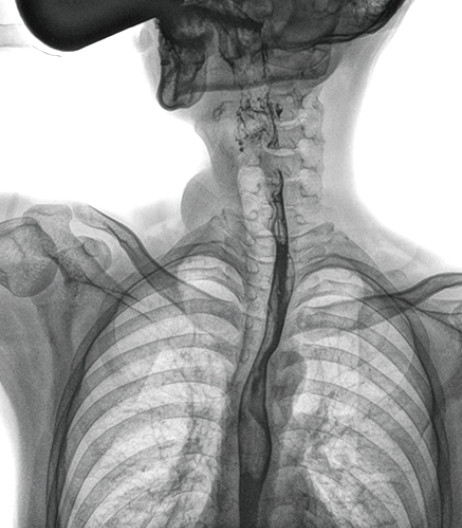

食管造影是食管病變的基本檢查方法,可以發(fā)現(xiàn)食管癌的特征性改變——食管粘膜的中斷和破壞,病人常感覺吞咽障礙,此特征在臨床中最常見,也是早期食管癌的典型表現(xiàn)。一般伴隨的特征有管壁充盈缺損、龕影、軟組織塊影、食管腔狹窄等;在透視下還可看到食管壁僵硬、蠕動(dòng)緩慢等。

動(dòng)態(tài)DR能夠?qū)崿F(xiàn)大幅面透視,瞬時(shí)高清點(diǎn)片等。在食管造影檢查中,由于吞咽鋇劑后,造影劑流速非常快,在一個(gè)大幅面上方便觀察食管的病變。瞬時(shí)點(diǎn)片,可以實(shí)時(shí)捕捉到病變部位的影像,從而可以快速做出診斷。普利德多功能動(dòng)態(tài)DR擁有17×17英寸超大視野,一次曝光即可顯示整個(gè)食管,更方便觀察食管的病變,確定病變的范圍,對(duì)診斷和治療有重要參考價(jià)值。

與過去的數(shù)字胃腸機(jī)比較,動(dòng)態(tài)DR圖像分辨率高,對(duì)食管的全景觀察,局部粘膜破壞、中斷,管腔狹窄以及病灶范圍的顯示清晰度明顯更優(yōu)。

上消化道造影高清圖像

由此不難看出,動(dòng)態(tài)DR在食管造影的臨床應(yīng)用上,相比于其他檢查手段,成像清晰、應(yīng)用便捷,而且能夠充分顯示食管的局部和整體結(jié)構(gòu)形態(tài),并以此揭示相關(guān)形態(tài)和功能性改變,更有利于助力實(shí)現(xiàn)精準(zhǔn)診斷。